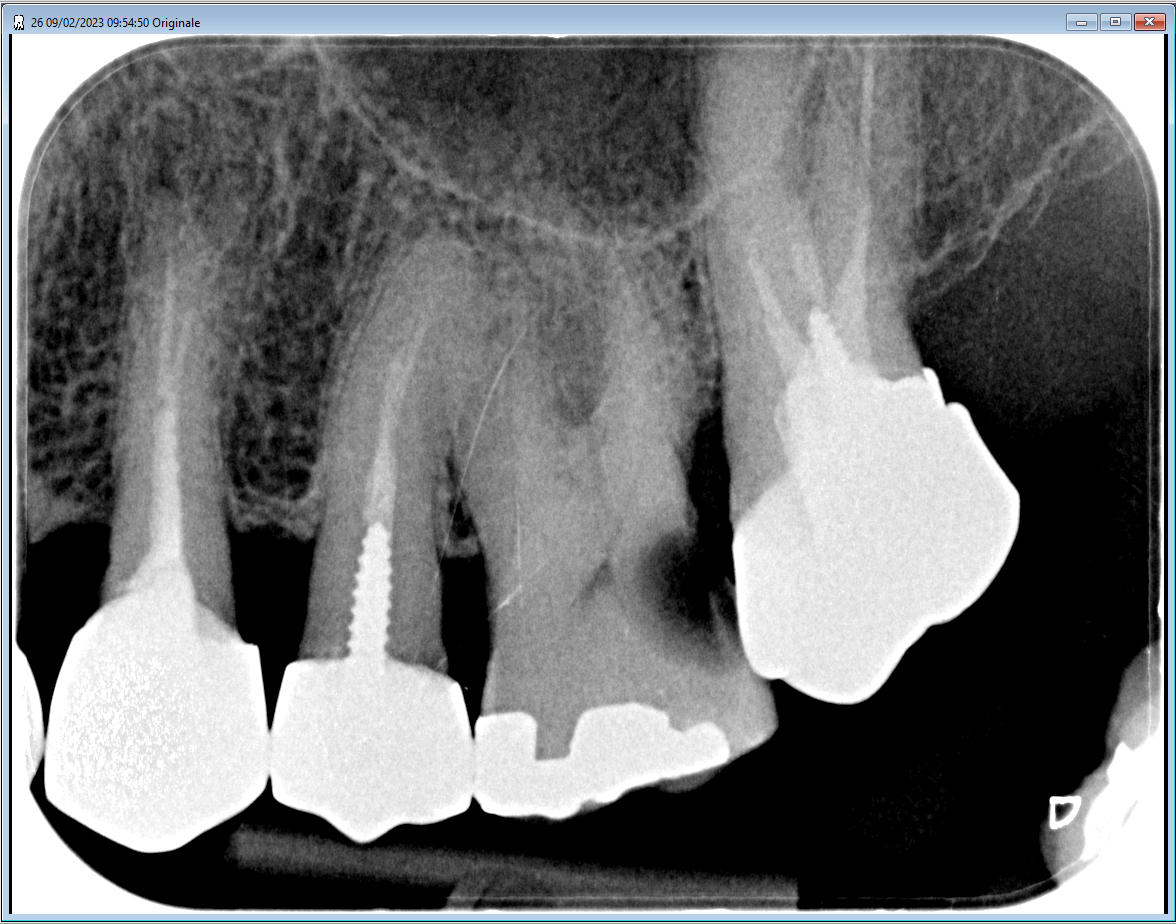

la par exemple a l'instant:

0.08s 70kv 8mA